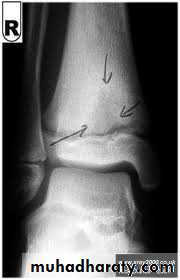

• Imaging:

• X-ray:

• Soft tissue swelling.

• The earliest change is diffuse bone rarefaction throughout a wide area of bone adjacent to the joint.

• In early stages: joint space retained.

• In later stages:

• Narrowing and irregularity of the joint space.

• Bone destruction on both sides of the joints.

• Cyctic changes may appear.